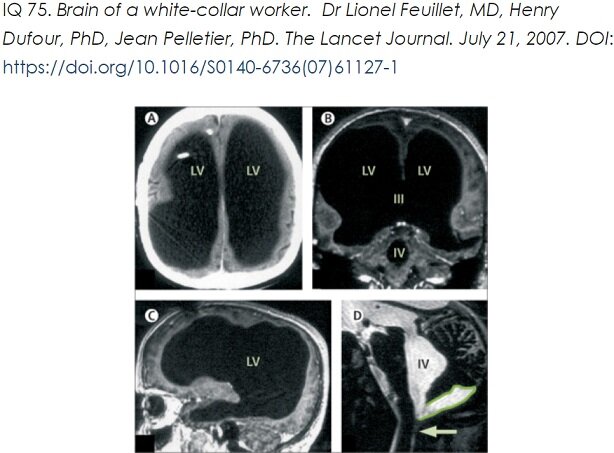

P.S. Если обратить внимание на самый первый снимок А и Б, там есть области, где и сама кора (серое вещество) совсем смято, или отсутствует. Черный фон расширившихся желудочков мозга соприкается с черепом. А это снимки вполне функционального клерка, описанные в статье в Ланцете. Этот момент я пока не успела обсудить. Возможно, кора сместилась куда-то еще, и была бы видна с другого МРТ среза, но такое смещение и его причины довольно трудно себе представить.

Несколько лет назад меня заинтересовали случаи гидроцефалии (из научных публикаций), при которых визуально на снимках МРТ практически отсутствует мозг, но при этом люди оставались психически сохранны, кто-то обратился к врачу по поводу появившейся слабости в ноге или руке, кто-то чувствовал себя прекрасно и учился на 2-м курсе математического факультета, и был направлен на МРТ просто в связи с крупным размером головы, и т.п.